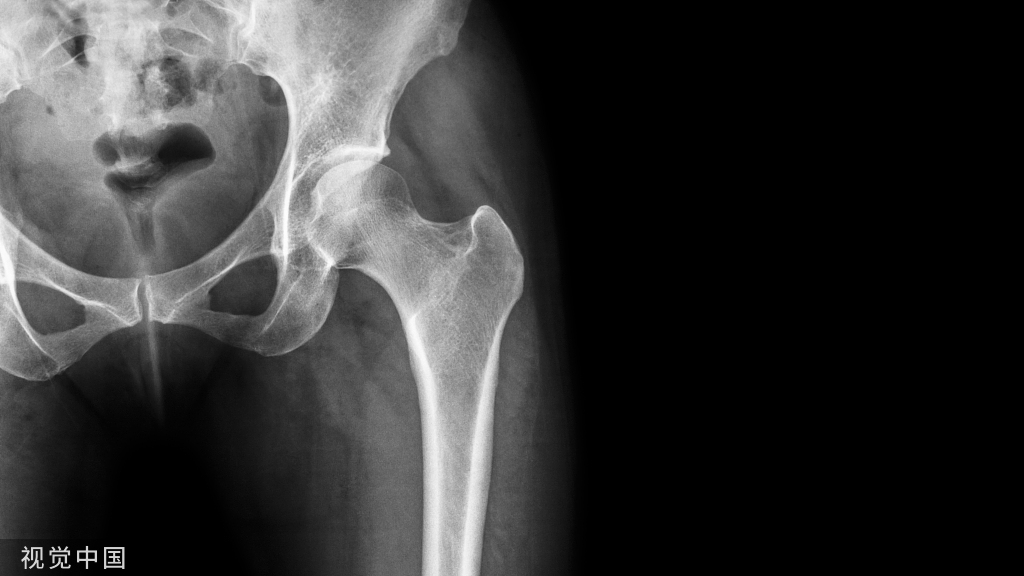

(一)地图样破坏  地图样破坏是指肿瘤组织在一个局部呈团块状生长造成界限清楚的骨质破坏(图 1、图 2、图 3、图 4)。

病灶可位于骨的中心或一侧部位,呈圆形、卵圆形密度减低区,与正常骨质分界清晰,边缘可有或无硬化带围绕,骨的形态无变化,病灶内可完全透亮或可见粗细不均、大小不等的残留骨嵴,内缘可光滑或呈分叶状压迹。

地图样破坏见于大多数良性肿瘤和肿瘤样病变如单纯性骨囊肿、骨纤维结构不良、血管瘤等、也可见于部分恶性骨肿瘤如骨转移瘤、骨髓瘤等。

图 1  地图样破坏:单纯性骨囊肿

图 2  地图样破坏:骨纤维结构不良

图 3  地图样破坏:骨内脂肪瘤

图 4 地图样破坏:骨转移瘤